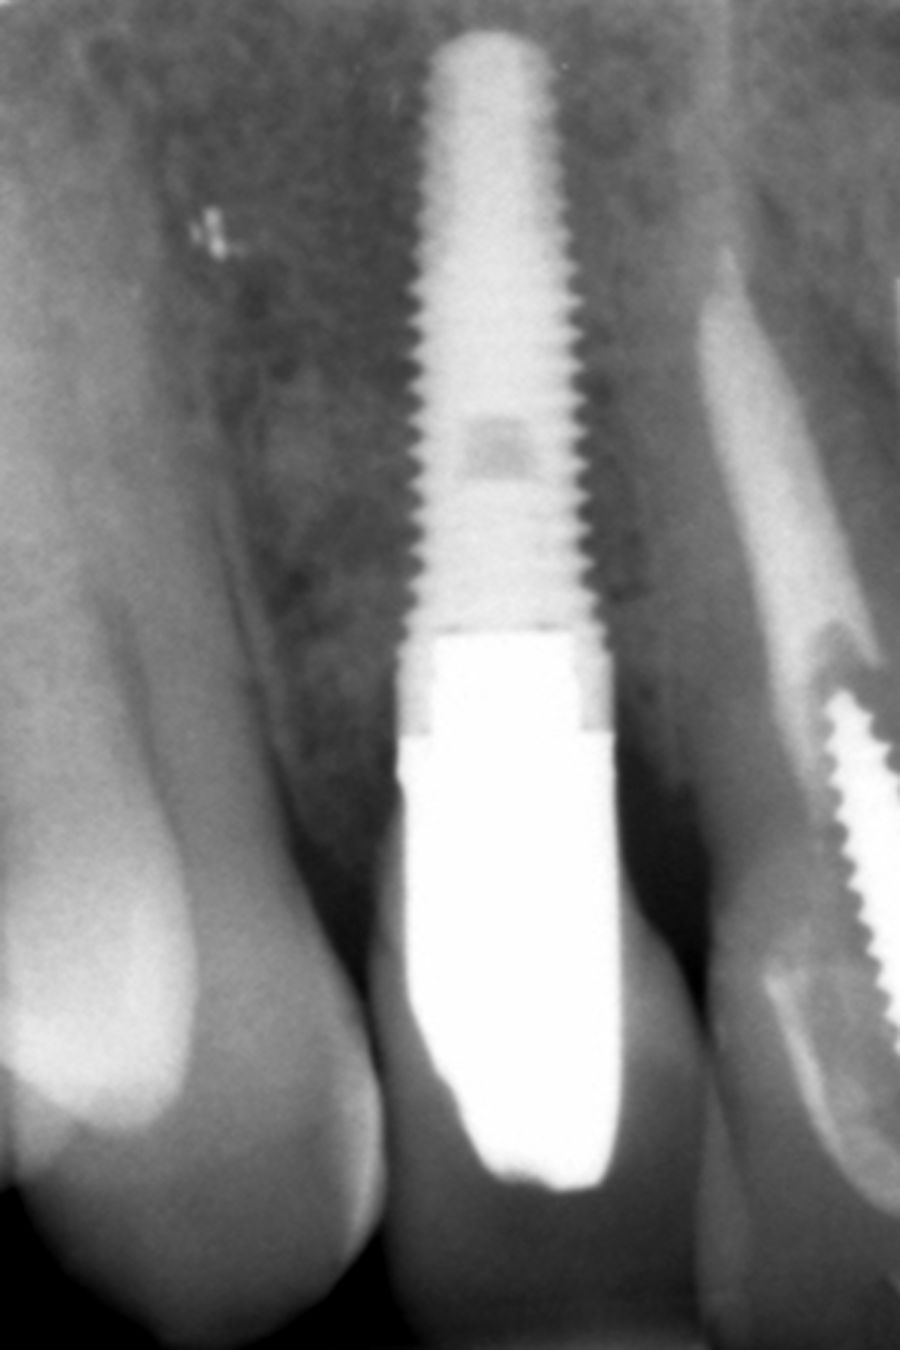

Four months later, a new dental cone-beam is performed to quantify the gain obtained in width with the regenerative procedure. It is observed in the sectional cut that a crest width of more than 7 mm and a complete regeneration of the alveolar ridge has been achieved, allowing the insertion of a new dental implant in the adequate position (Figure 10). In the surgical reentry, the information of the Cone-Beam is verified with a total integration of the graft material, as shown in the clinical images at the time of lifting the flap for the insertion of the implant (Figures 11 and 12). The microscrew is removed and the implant is placed, which is performed by vestibular compression of the graft to gain in this manner even more contour in this area (Figure 13). The implant is left in a surgical phase, with a low healing abutment that allows a subsequent location of the same without an aggressive soft tissue surgery when the construction of the prosthesis is initiated. The provisional crown remains as an extension from the tooth 1.1.